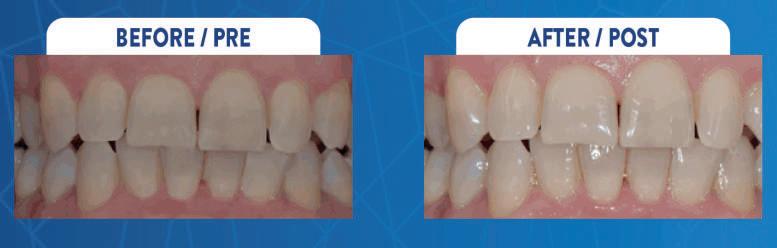

Luca Tacchini, Odt – erosioni da perimolisi

I primi studi effettuati con analisi spettrofotometrica hannodimostrato efficacia del prodotto, determinando variazioni significative in linea con le modifiche che aumentano la percezione di sbiancamento dentario da parte del paziente. In particolare, lo sbiancamento dentario deve portare ad un aumento della luminosità, una diminuzione del giallo e una riduzione del rosso. Tutte le variabili hanno mostrato una differenza statisticamente significativa (p<0,05).